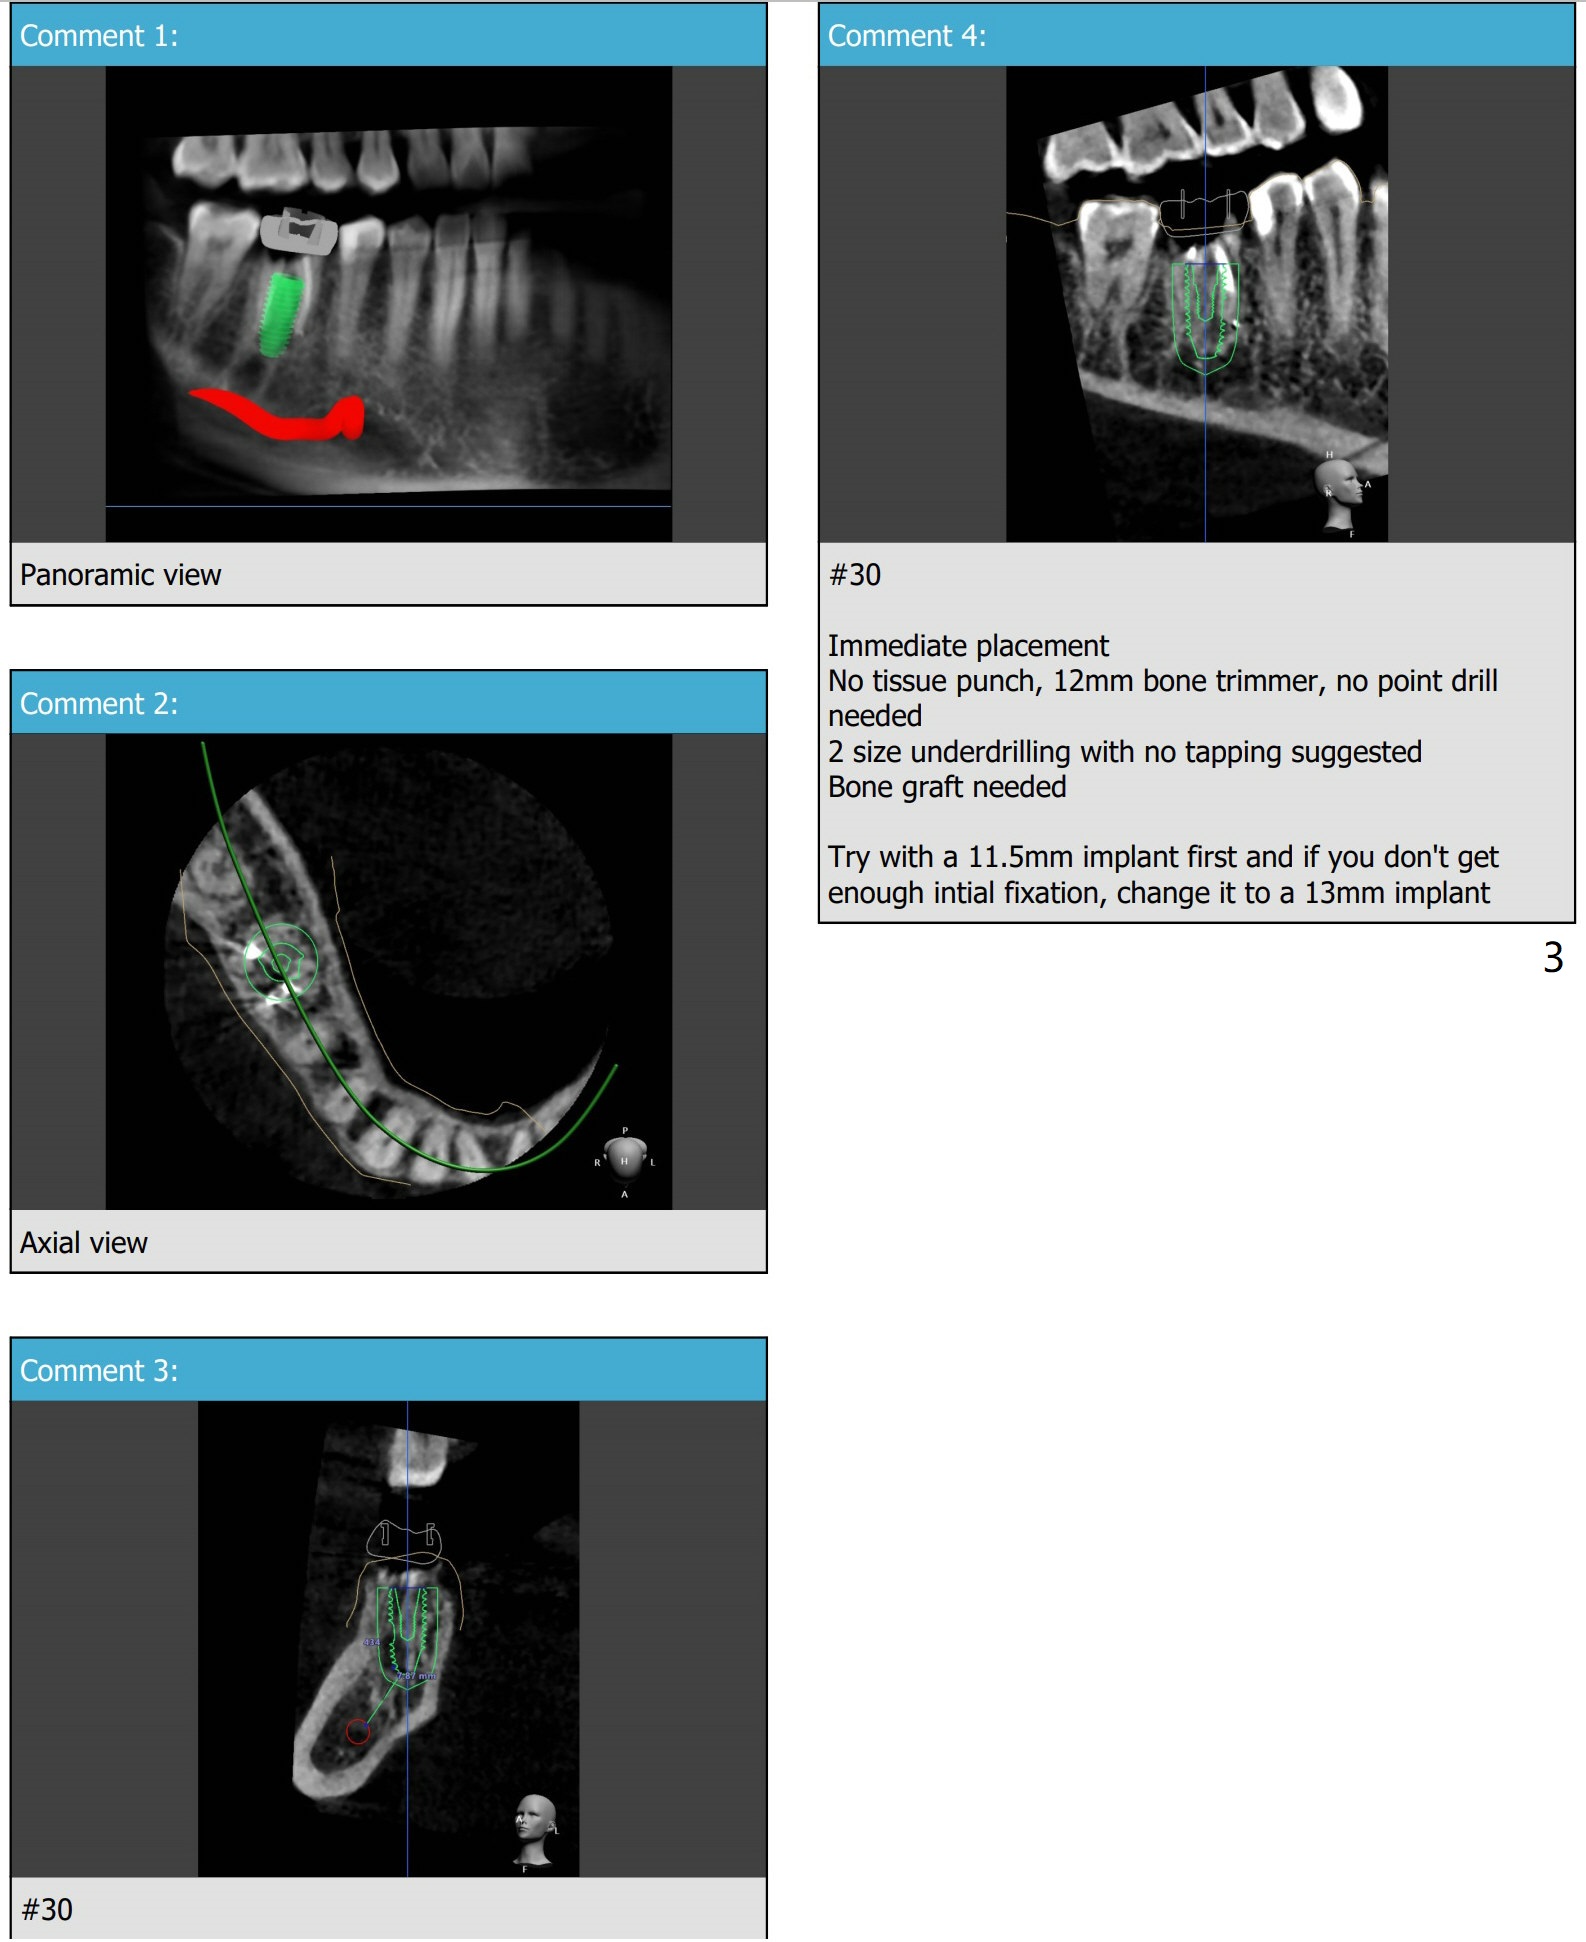

两种长度植体

暴露中隔,保留牙根,钻洞(避免偏移),取出牙根,植入植体。After the first option, place a 4.5x10 mm dummy implant.